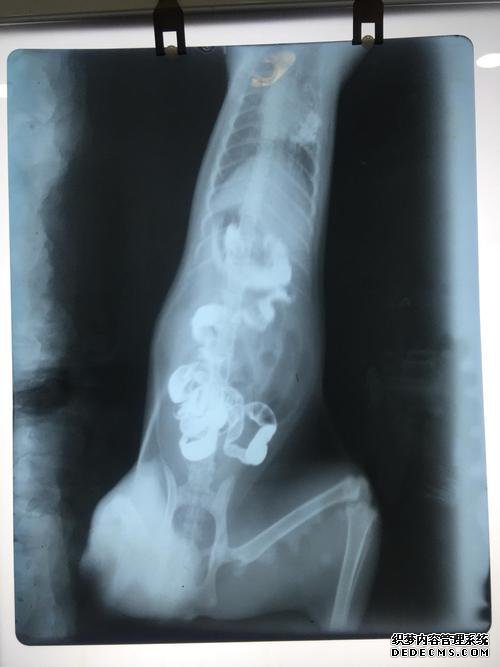

钡食物检查主要是胃肠道检查的方法,即先做相关准备工作,然后用X射线照射的检查。此类考试的费用因考试地点而异,并且会有所不同。

检查消化道通常在200元左右。观察消化道的费用通常在300元左右。

该病的诊断不如胃肠道内窥镜检查准确,但是钡食物测试是非常安全的,但它也可以有效地发现胃肠道疾病。